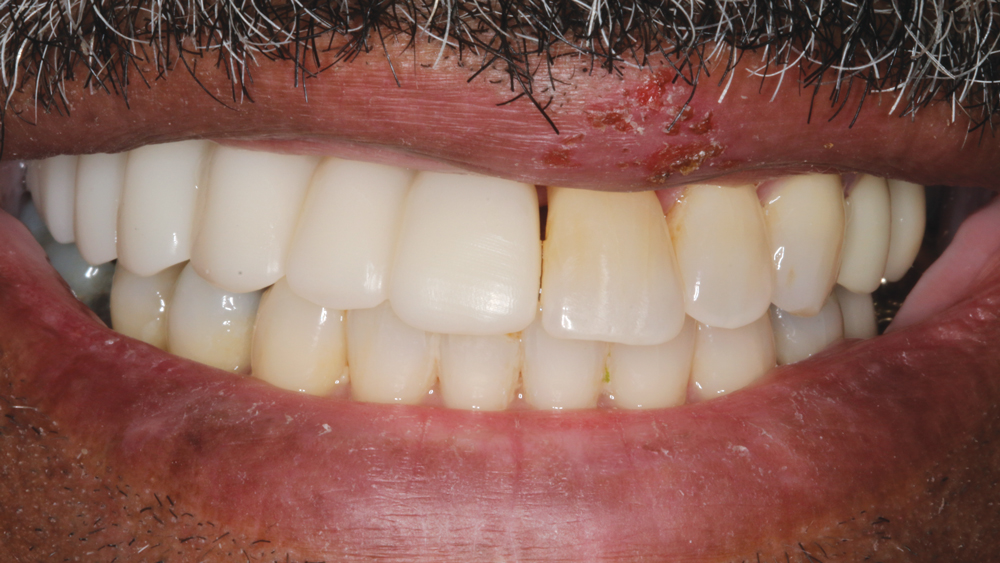

RESTORATIVE TECHNIQUES FOR ESTHETICS AND OCCLUSION

Esthetics and occlusion can be challenging in these types of cases. Restoring half an arch and trying to mirror the contralateral soft tissue and dentition with proper contours and shade requires patience and resolve. The lab provided a PMMA try-in prosthesis, which I evaluated with Weldon. The try-in allowed us to easily resolve any discrepancies with the prosthetic design and develop ideal occlusion. Once Weldon agreed on the esthetics, the PMMA provisional was returned to the lab and duplicated in BruxZir Solid Zirconia. This extra step eliminates excessive chairside adjustments upon seating of the final prosthesis.

The PMMA try-in prosthesis ... allowed any necessary adjustments to easily be made to the prosthetic design prior to milling the final BruxZir restoration.

BruxZir Solid Zirconia has proven to be extremely strong yet compatible with opposing natural dentition; the material exhibits minimal wear on the opposing enamel. Its color and shading are extremely natural in appearance, and I have no concerns about chipping or cracking of the material over time. The final seating of the prosthesis was straightforward, and I have confidence that the material is a long-lasting solution. Weldon was thrilled with the final restoration, as we were able to surpass his expectations and provide him with a fixed, functional, esthetic result.